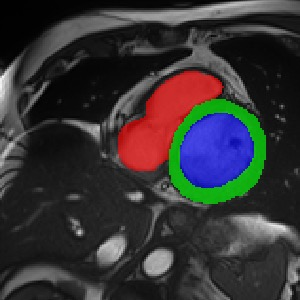

Transformers, the default model of choices in natural language processing, have drawn scant attention from the medical imaging community. Given the ability to exploit long-term dependencies, transformers are promising to help atypical convolutional neural networks (convnets) to overcome its inherent shortcomings of spatial inductive bias. However, most of recently proposed transformer-based segmentation approaches simply treated transformers as assisted modules to help encode global context into convolutional representations without investigating how to optimally combine self-attention (i.e., the core of transformers) with convolution. To address this issue, in this paper, we introduce nnFormer (i.e., Not-aNother transFormer), a powerful segmentation model with an interleaved architecture based on empirical combination of self-attention and convolution. In practice, nnFormer learns volumetric representations from 3D local volumes. Compared to the naive voxel-level self-attention implementation, such volume-based operations help to reduce the computational complexity by approximate 98% and 99.5% on Synapse and ACDC datasets, respectively. In comparison to prior-art network configurations, nnFormer achieves tremendous improvements over previous transformer-based methods on two commonly used datasets Synapse and ACDC. For instance, nnFormer outperforms Swin-UNet by over 7 percents on Synapse. Even when compared to nnUNet, currently the best performing fully-convolutional medical segmentation network, nnFormer still provides slightly better performance on Synapse and ACDC.